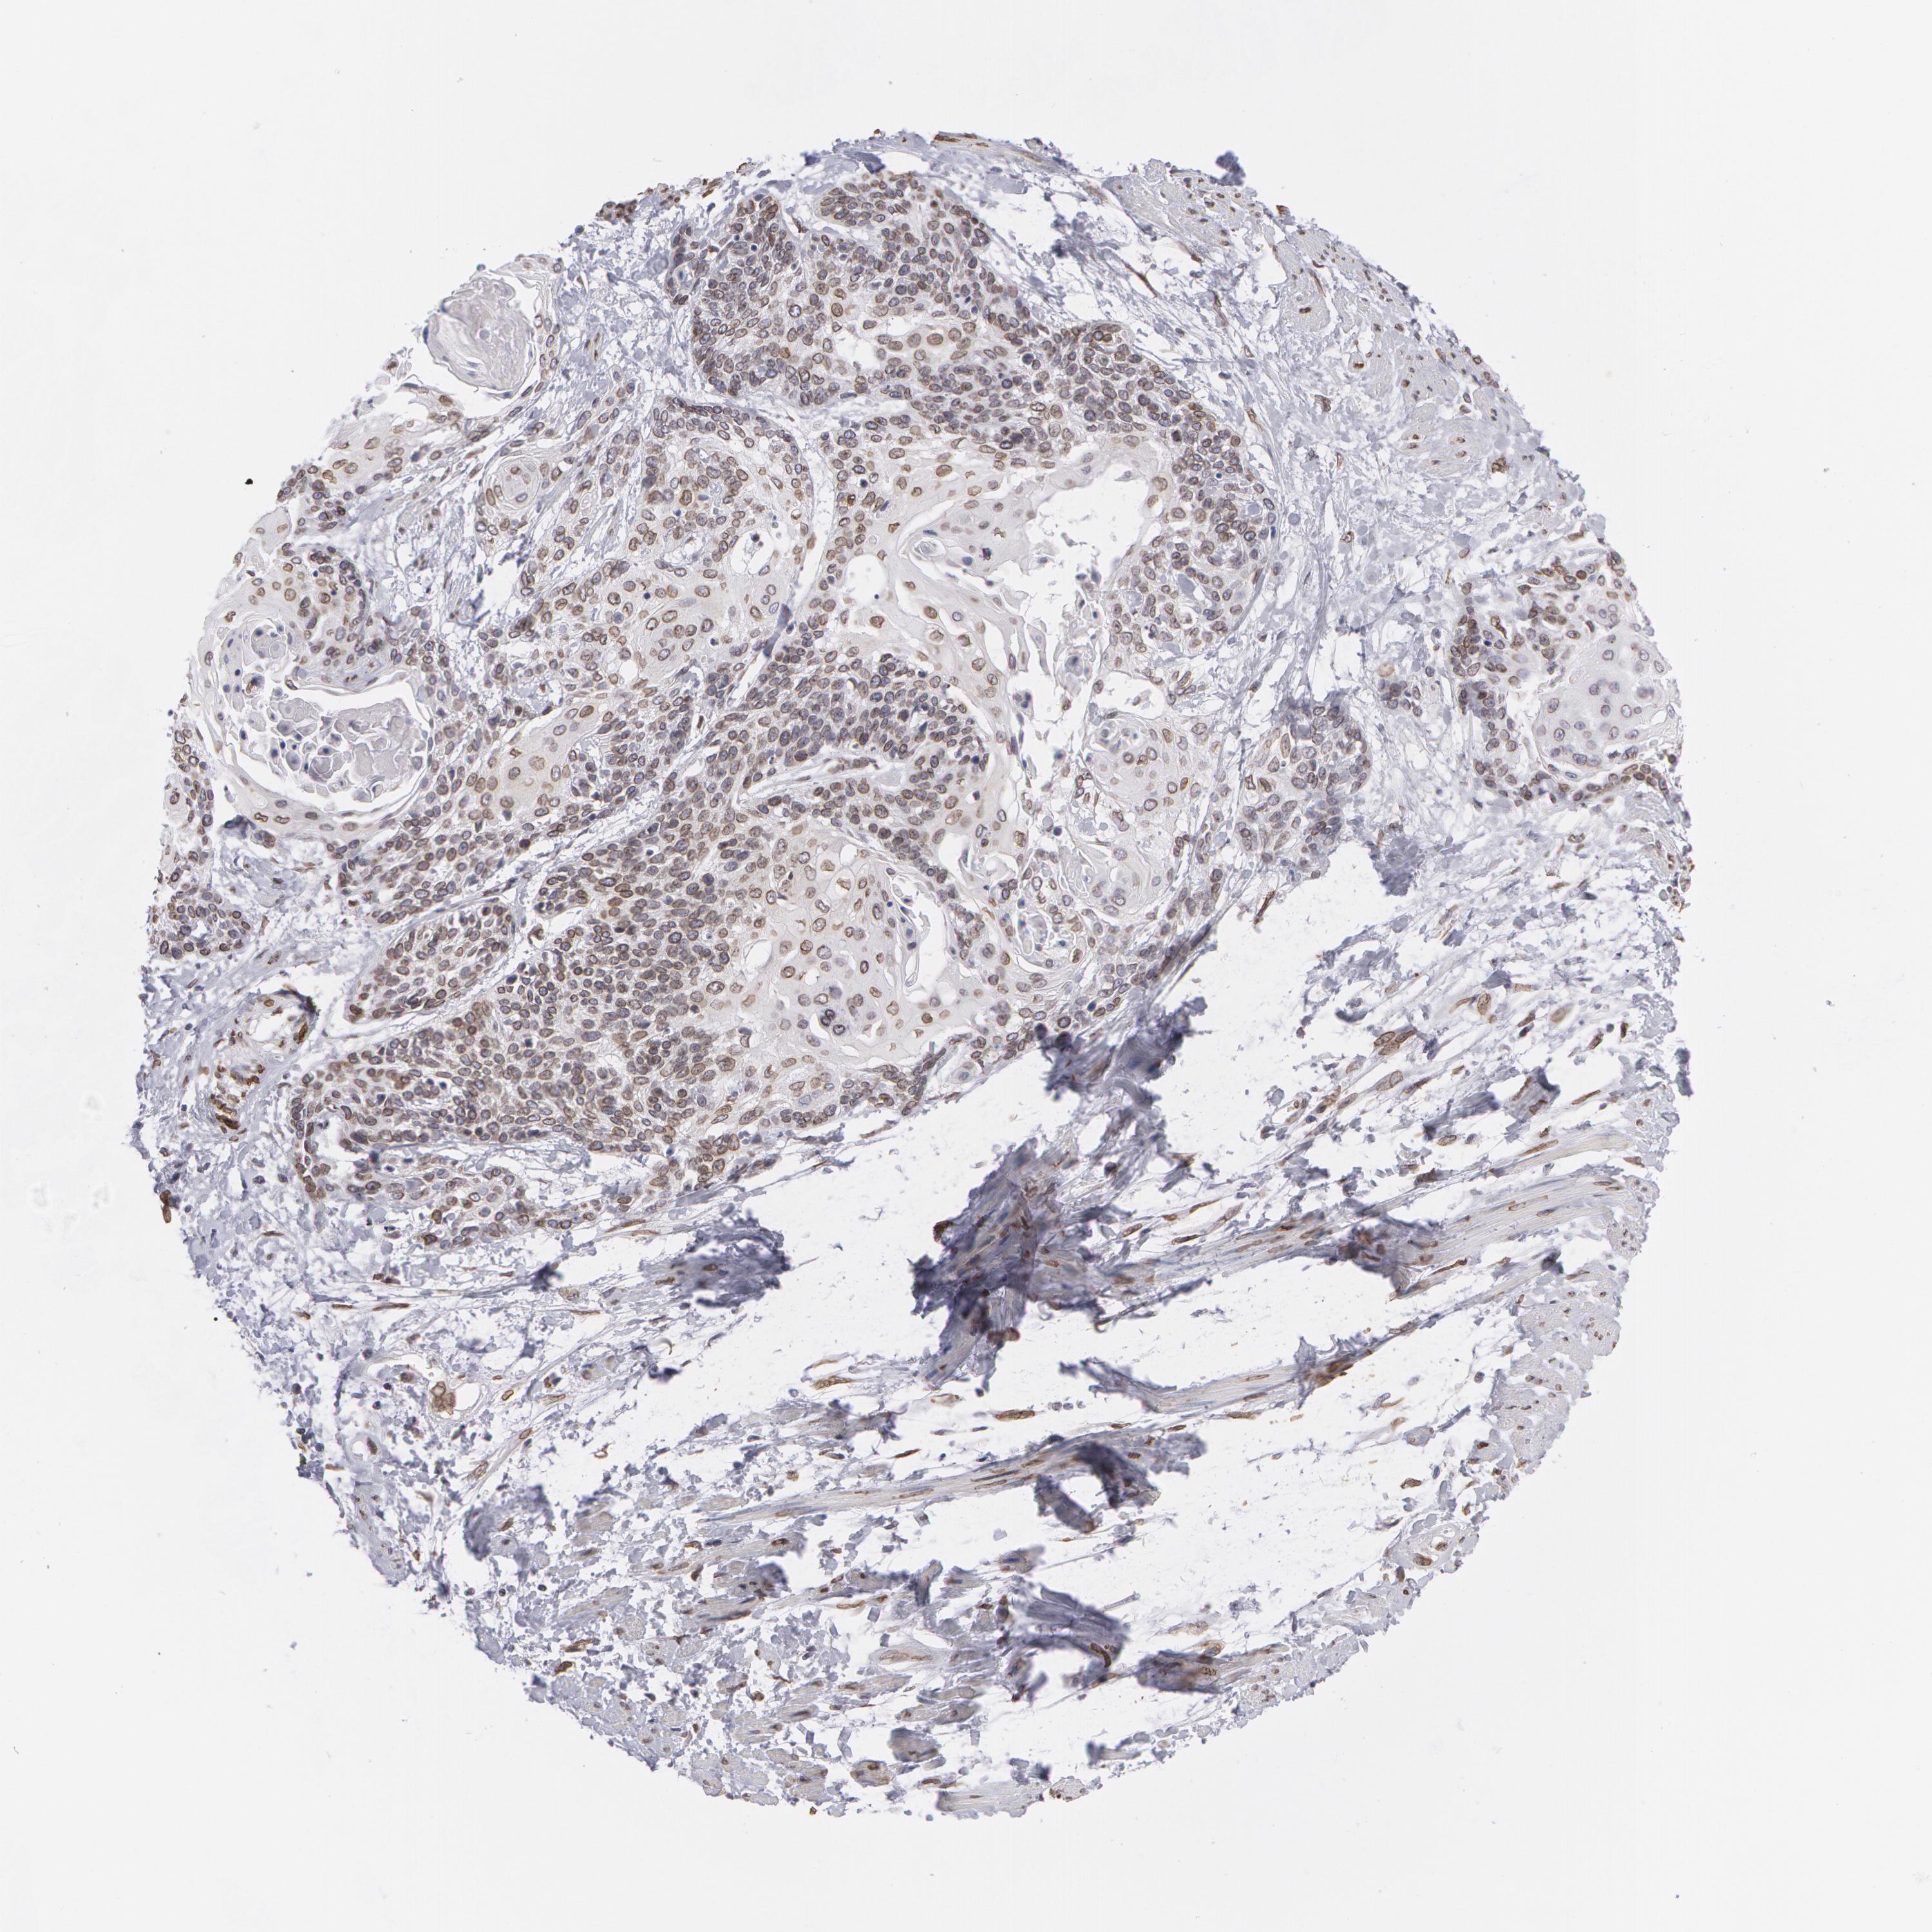

CERVICAL CANCER - Protein expressioni

A mouse-over function shows sample information and annotation data. Click on an image to view it in a full screen mode. Samples can be filtered based on level of antibody staining by selecting one or several of the following categories: high, medium, low and not detected. The assay and annotation is described here.

Note that samples used for immunohistochemistry by the Human Protein Atlas do not correspond to samples in the TCGA dataset.

Antibody stainingi

Antibody staining in the annotated cell types in the current human tissue is reported as not detected, low, medium, or high, based on conventional immunohistochemistry profiling in selected tissues. This score is based on the combination of the staining intensity and fraction of stained cells.

Each image is clickable and will lead to virtual microscopy that enables deeper exploration of all samples and also displays staining intensity scores, fraction scores and subcellular localization as well as patient and tissue information for each sample.

Antibody HPA000609

Antibody CAB001545

Antibody CAB002029

Antibody CAB062552

Squamous cell carcinoma, NOS